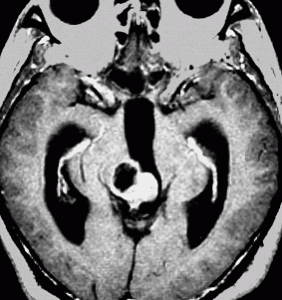

成人女性の松果体細胞腫で充実性腫瘍です。多少凹凸がありますがだいたい楕円形。中脳水道が閉塞して軽度の水頭症(頭の中に髄液が溜まる)になってきています。急性水頭症で急変して意識障害になることがありますので,迷わず摘出するか,第3脳室開窓術 ETVをしてから経過観察します。